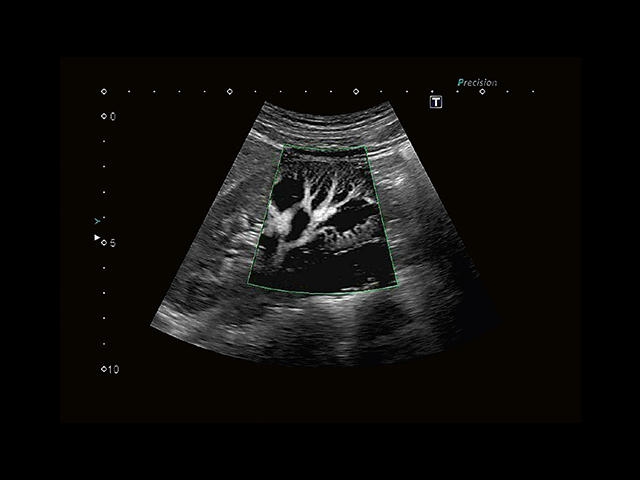

Aplio 500 – ультразвуковой сканер премиум класса, сочетающий в себе быстродействие диагностики и отличное качество визуализации. Более 30 датчиков на выбор, в т.ч. матричные, монокристаллические, 4D, эндоскопические для любых типов исследований. Ультразвуковой сканер позволяет изучать анатомические структуры в высоком разрешении.

Обновленная версия легендарного УЗ-сканера. Стационарный аппарат экспертного класса Aplio 500 Toshiba NEW, визуализирует анатомические структуры в высоком разрешении. Модель позволяет выявить микрокальцификаты, новообразования, нарушения в работе сердца, сосудов и мышц. Присутствует функция виртуальной эндоскопии, 4D-сканирования, эластометрии тканей, УЗИ с контрастированием. За повышение качества изображения отвечают технологии ApliPure и Superb Microvascular Imaging. Первая задействует возможности пространственного и частотного кодирования, формирует цельный визуальный ряд с сохранением клинических маркеров. Вторая улучшает отображение микрососудистого русла, используя доплеровский эффект. Модель оснащена 21-дюймовым монитором, имеет 4 активных порта. Возможно подключение педиатрических, интраоперационных, лапароскопических и чреспищеводных датчиков.